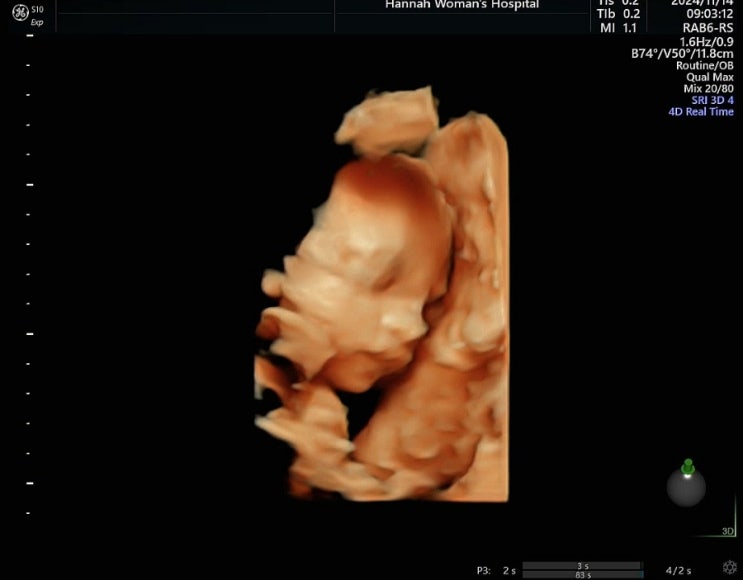

임신 25주차 ~ 28주차(갑작스러운하혈, 본격 이사준비, 임당확정, 새집에서 새출발)

11/9 ~ 11/15 PUREUM, 25weeksෆ 스벅 그란데사이즈로 자란 푸름이라니... 이제 채소나 과일크기에서...